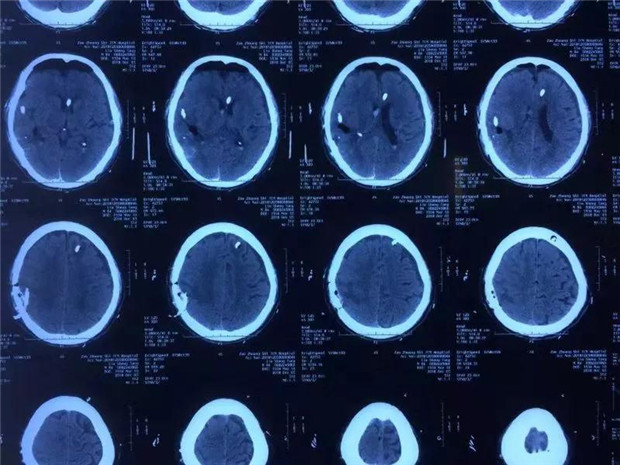

近日,我院神经外科接诊一位84岁高血压性脑出血老人。病人入院后已经昏迷,肢体瘫痪,随即出现脑疝。颅脑CT显示右侧颞、顶叶出血并形成占位性血肿,同时血肿破入脑室系统,估算出血量约70毫升。

患者术前脑CT

患者术后脑CT